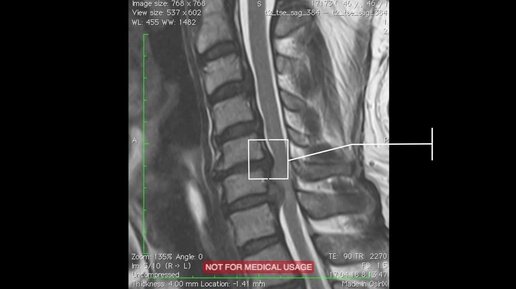

История человека с грыжей 12 мм шейного отдела позвоночника на уровне С6-С7